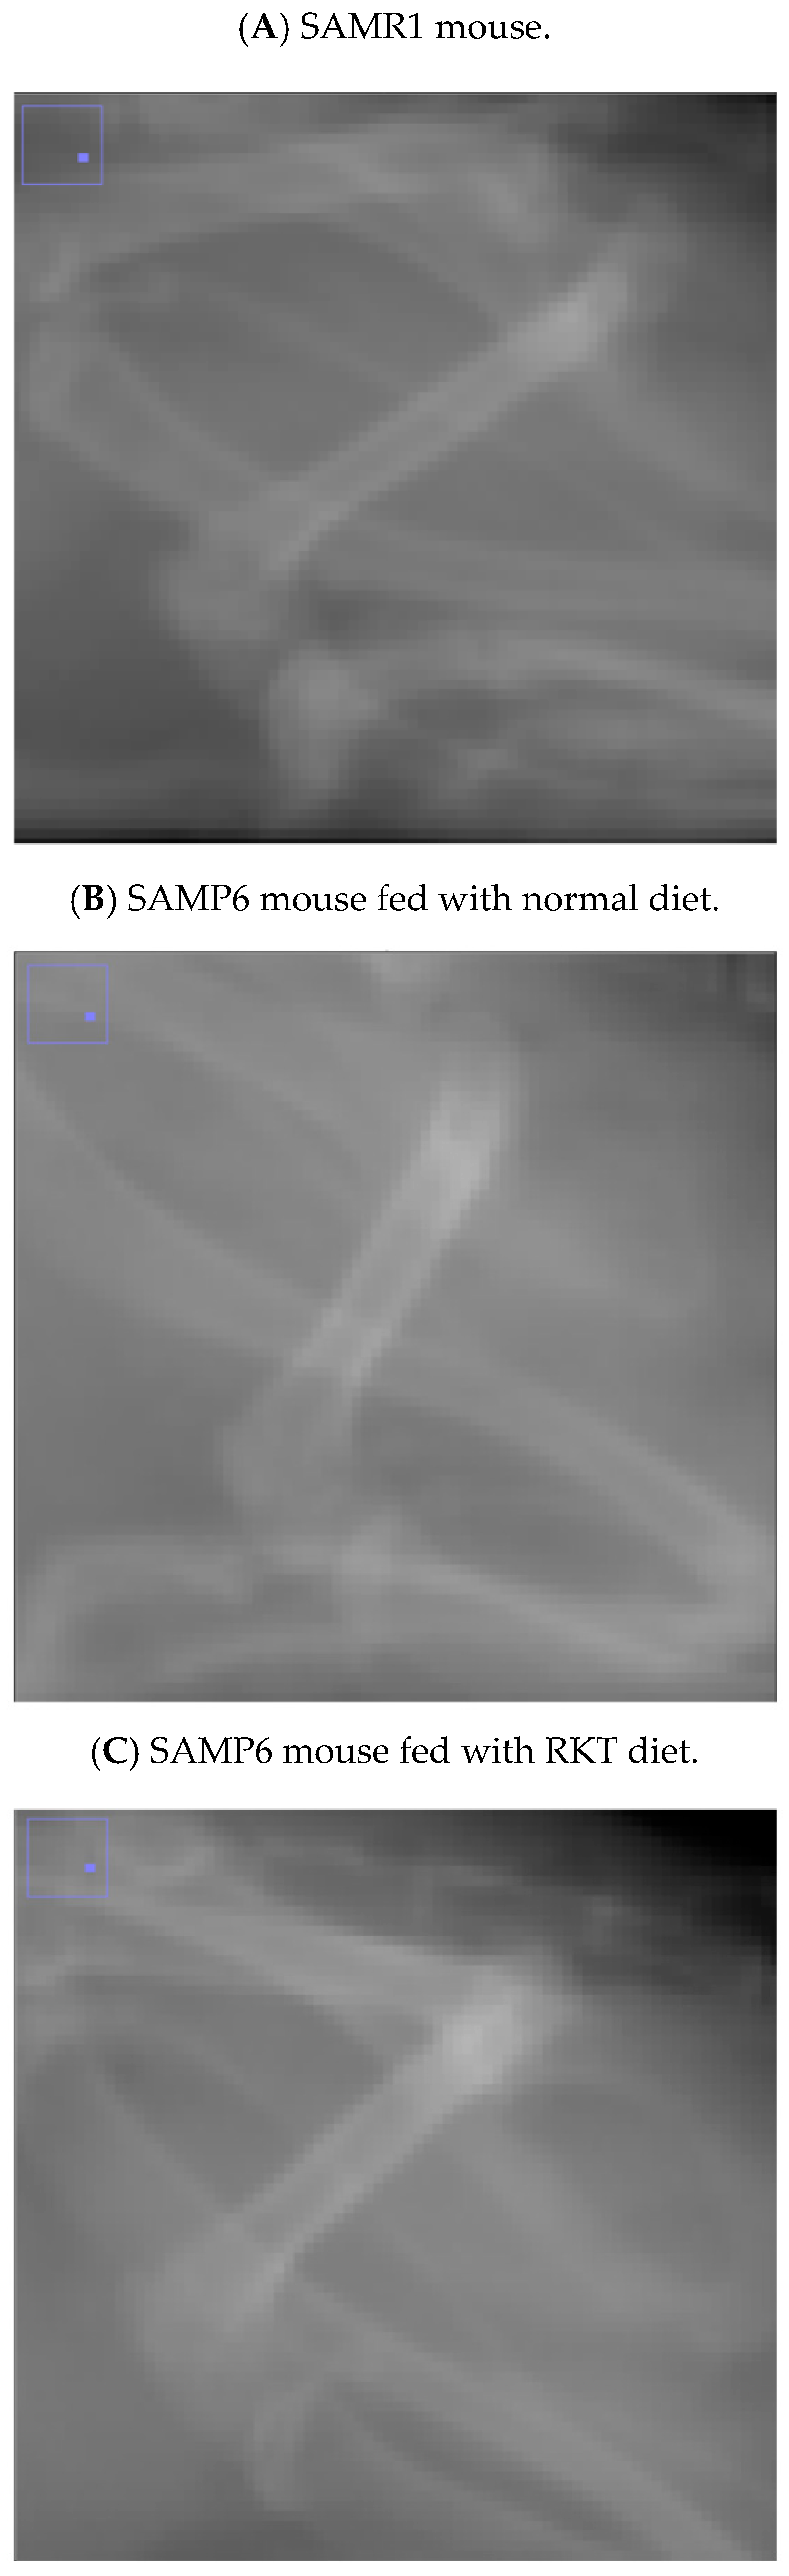

Figure 2. The X-ray photographs show representative femur images in a 150-day-old (A) SAMR1 mouse, (B) a SAM P6 mouse fed the normal diet, and a (C) SAMP6 mouse fed the Rikkunshi-To (RKT) diet.